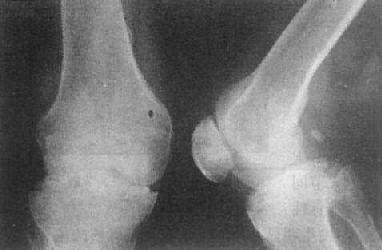

骨巨细胞瘤以20~40岁为常见,好发于四肢长骨,以股骨下端、胫骨上端和桡骨下端为常见。主要临床表现为局部疼痛、肿胀和压痛。较大肿瘤可有局部皮肤发热和静脉曲张。

长骨巨细胞瘤的X线表现多较典型(图2-1-23),常侵犯骨端,症变直达骨性关节面下。多数为偏侧性破坏,边界清楚。瘤区X线表现可有两种类型,较多的病例破坏区内可有数量不等、比较纤细的骨嵴。X线上可见似有分隔成为大小不一的小房征,称为分房型。少数病例破坏区内无骨嵴,表现为单一的骨质破坏,称为溶骨型。病变局部骨骼常呈偏侧性膨大,骨皮质变薄,肿瘤明显膨胀时,周围只留一薄层骨性包壳。肿瘤内无钙化或骨化致密影,邻近无反应性骨膜增生。边缘亦无骨硬化带,如不并发骨折也不出现骨膜增生。破坏区骨性包壳不完整,并于周围软组织中出现肿块者表示肿瘤生长活跃。肿瘤边缘出现筛孔状和虫蚀状骨破坏,骨嵴残缺紊乱。侵犯软组织出现明确肿块者,则提示为恶性骨巨细胞瘤。肿瘤一般不穿破关节软骨,但偶可发生,甚至越过关节侵犯邻近骨骼。

图2-1-23 桡骨巨细胞瘤桡骨骨端边界清楚的骨破坏,

其中有多个骨隔将骨破坏区分成多个小房,病变有膨胀性